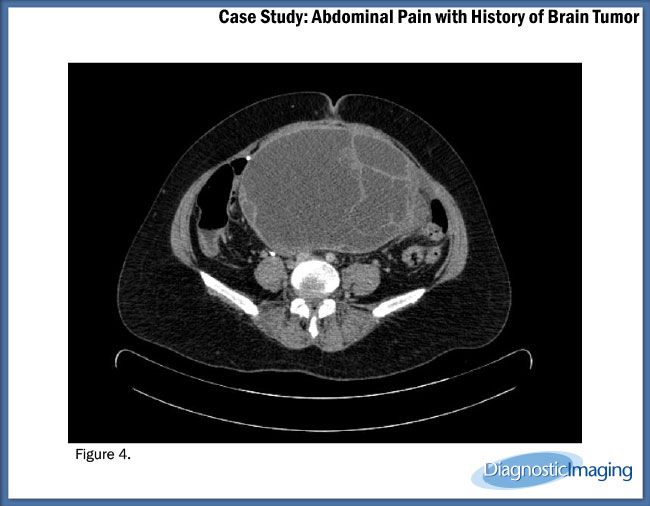

Case History: A 45-year-old patient with history of brain tumor with ventriculoperitoneal shunt presented with complaints of abdominal pain.